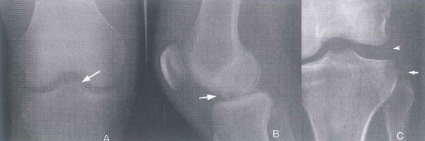

Hình 10.1. Tổn thương xương diện bám dây chằng trong trật khớp gối A,B. Bong điếm bám dây chằng chéo trước c. Bóng điểm bám dây chằng bên ngoài và rộng khe khớp bên ngoài